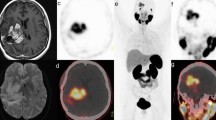

Five to 21 days after balloon dilatation, [18F]DCFPyL binding was noticeable in the entire ipsilateral CCA, while binding in the contralateral CCA was weak or even absent (Fig. 1a,b). The mean ratio between ipsi- and contralateral CCA was 1.67 ± 0.39, which was significantly different from µ = 1.0 (p < 0.0001; one sample t-test). Comparison of the arterial tracer uptake between the ipsi- and contralateral CCA revealed significantly higher uptake values for the ipsilateral CCA (0.030 ± 0.026%ID/cm3 vs. 0.020 ± 0.021%ID/cm3, p = 0.0004; paired t-test). Blocking of GCPII binding sites with PMPA in two animals resulted in strong reduction of ipsilateral arterial tracer binding to 0.0008 and 0.0004%ID/ccm3, respectively (Fig. 1c).

Increased GCPII-expression in the rat CCA after dilatation with a balloon catheter. (a) Schematic drawing of the dilatation site (yellow) and the cervical ganglia (red and green) used as landmarks. (b) [18F]DCFPyL-PET image five days post-op. The image was tilted (see insert, level a–d) so that the CCA was oriented in the horizontal plane. Red squares indicate position of the VOIs. (c) Blocking experiment with PMPA (23 mg/kg BW), injected together with [18F]DCFPyL. (d) Image of a different rat seven days post-op. in horizontal and transverse view. E: Plotting of VOI ratios (ipsi-/contralateral) over time after dilatation. Blue lines indicate animals that were measured twice. Abbreviations: B: brain; CCA: common carotid artery; ECA: external carotid artery; ICA: internal carotid artery; ICG: inferior cervical ganglion; SCG: superior cervical ganglion; SG: salivary gland; SJ: shoulder joint. SpG: Spinal ganglia. Scale bars: 1 cm.